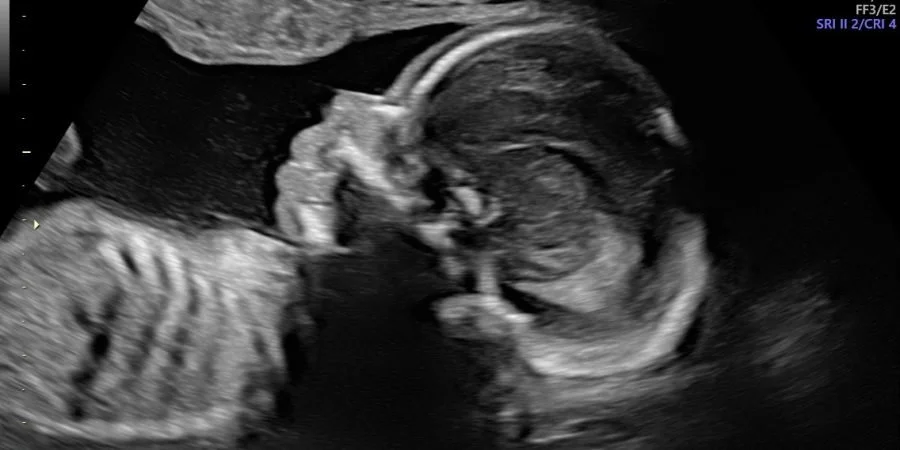

Overall, I’m feeling much better about this pregnancy now that I’ve officially reached my halfway point. I’ll be 21 weeks on Tuesday. I’m also feeling our baby more and more each day as he or she grows—and hubby has finally been able to feel the baby kick from the outside.